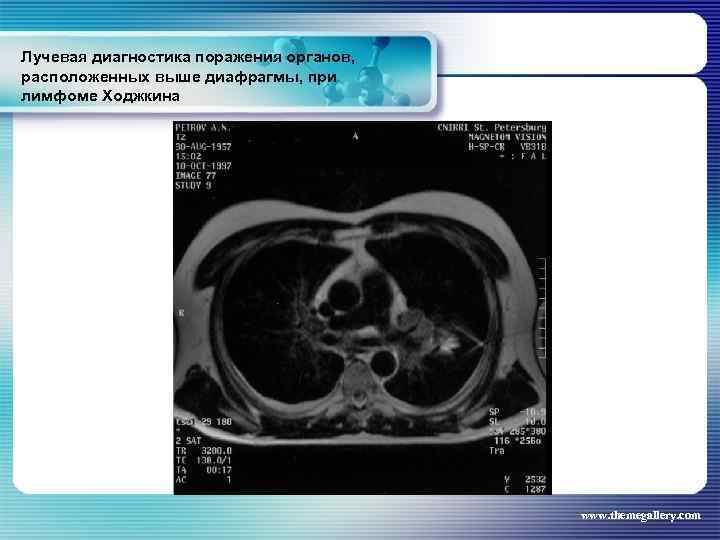

Лучевая диагностика поражения органов, расположенных выше диафрагмы, при лимфоме Ходжкина Частота поражения органов грудной полости при лимфоме Ходжкина: поражение средостения легких плевры грудной стенки - 66, 7 % 33, 75% 5, 3% 1, 8% www. themegallery. com

Лучевая диагностика поражения органов, расположенных выше диафрагмы, при лимфоме Ходжкина Частота поражения органов грудной полости при лимфоме Ходжкина: поражение средостения легких плевры грудной стенки - 66, 7 % 33, 75% 5, 3% 1, 8% www. themegallery. com

Лучевая диагностика поражения органов, расположенных выше диафрагмы, при лимфоме Ходжкина www. themegallery. com

Лучевая диагностика поражения органов, расположенных выше диафрагмы, при лимфоме Ходжкина www. themegallery. com

Лучевая диагностика поражения органов, расположенных выше диафрагмы, при лимфоме Ходжкина www. themegallery. com

Лучевая диагностика поражения органов, расположенных выше диафрагмы, при лимфоме Ходжкина www. themegallery. com

Лучевая диагностика поражения органов, расположенных выше диафрагмы, при лимфоме Ходжкина www. themegallery. com

Лучевая диагностика поражения органов, расположенных выше диафрагмы, при лимфоме Ходжкина www. themegallery. com

Лучевая диагностика поражения органов, расположенных выше диафрагмы, при лимфоме Ходжкина www. themegallery. com

Лучевая диагностика поражения органов, расположенных выше диафрагмы, при лимфоме Ходжкина www. themegallery. com

Лучевая диагностика поражения органов, расположенных выше диафрагмы, при лимфоме Ходжкина www. themegallery. com

Лучевая диагностика поражения органов, расположенных выше диафрагмы, при лимфоме Ходжкина www. themegallery. com

Лучевая диагностика поражения органов, расположенных выше диафрагмы, при лимфоме Ходжкина www. themegallery. com

Лучевая диагностика поражения органов, расположенных выше диафрагмы, при лимфоме Ходжкина www. themegallery. com

Лучевая диагностика поражения органов, расположенных выше диафрагмы, при лимфоме Ходжкина www. themegallery. com

Лучевая диагностика поражения органов, расположенных выше диафрагмы, при лимфоме Ходжкина www. themegallery. com

Лучевая диагностика поражения органов, расположенных выше диафрагмы, при лимфоме Ходжкина www. themegallery. com

Лучевая диагностика поражения органов, расположенных выше диафрагмы, при лимфоме Ходжкина www. themegallery. com

Лучевая диагностика поражения органов, расположенных выше диафрагмы, при лимфоме Ходжкина www. themegallery. com

Лучевая диагностика поражения органов, расположенных выше диафрагмы, при лимфоме Ходжкина www. themegallery. com

Лучевая диагностика поражения органов, расположенных выше диафрагмы, при лимфоме Ходжкина www. themegallery. com

Лучевая диагностика поражения органов, расположенных выше диафрагмы, при лимфоме Ходжкина www. themegallery. com

Лучевая диагностика поражения органов, расположенных выше диафрагмы, при лимфоме Ходжкина www. themegallery. com

Лучевая диагностика поражения органов, расположенных выше диафрагмы, при лимфоме Ходжкина www. themegallery. com

Лучевая диагностика поражения органов, расположенных выше диафрагмы, при лимфоме Ходжкина www. themegallery. com

Лучевая диагностика поражения органов, расположенных выше диафрагмы, при лимфоме Ходжкина www. themegallery. com